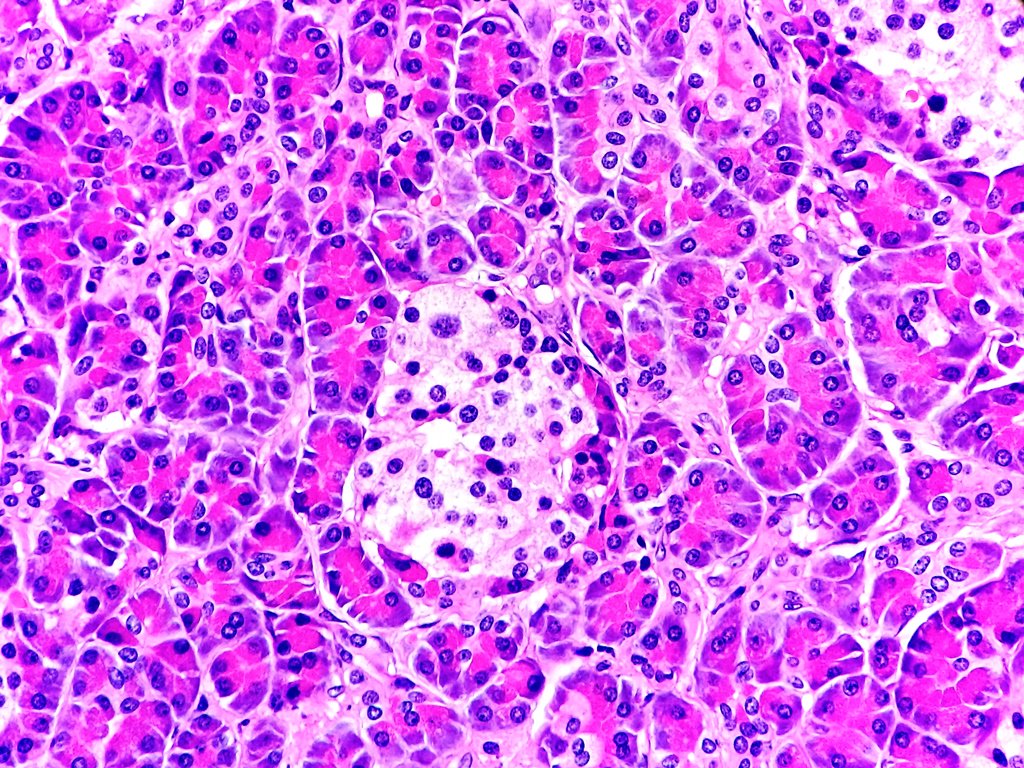

Páncreas normal. Acinos e islotes de Langerhans. Tinción HE

Anapat tweet mediaAnapat tweet mediaAnapat tweet media